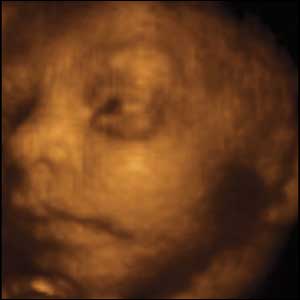

26 weeks gestation. 23cm from crown to rump.

9 of 10

Foetuses as young as 11 weeks have been seen with their thumbs in their mouths. This baby started out sucking his smallest toes and gradually moves on to suck a bigger and better toe.